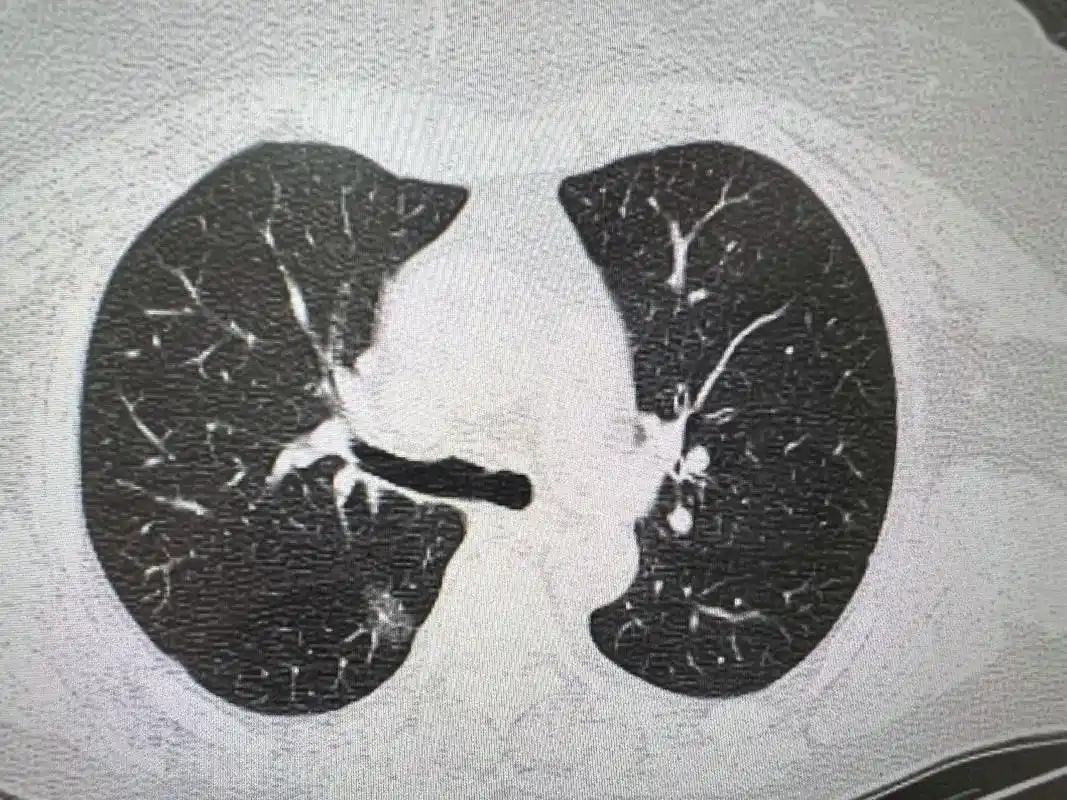

我院外四科完成首例右全肺切除术

右肺上叶支气管袖状切除淋巴结清扫术

在周胤江主任的主持下,胸外科完成一例高难度右肺上叶,右肺大疱切除术

哈医大二院今日一例右肺上叶尖段切除术 - 好大夫在线